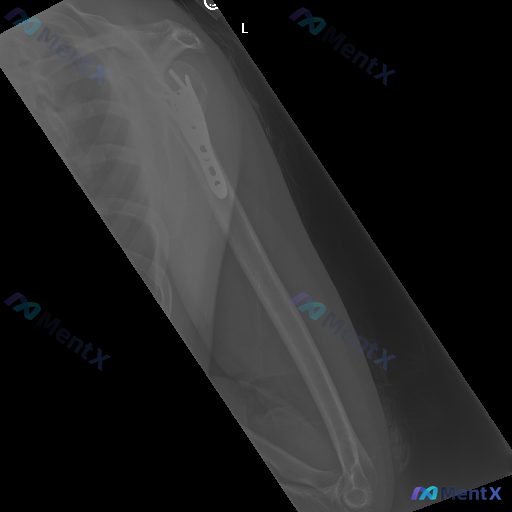

整理到一份左侧肩部及上臂的X线正位影像资料,情况如下: - 既往史背景:左侧肱骨近端有手术内固定史 - 本次X线表现: 1. 肱骨近端外侧可见解剖型锁定钢板及多枚螺钉,位置看起来稳固,没有明显断裂、松动或移位 2. 肱骨头及大结节区域有骨质结构重塑表现,骨折线愈合良好 3. 盂肱关节、肩锁关节对位关...